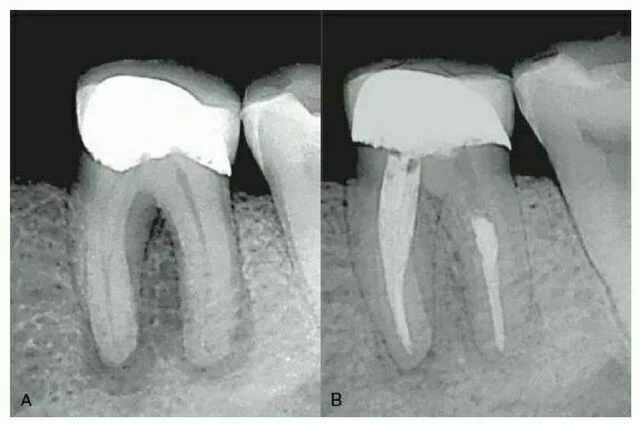

Tuy nhiên X-quang thông thường có thể không phải luôn xác định được đúng hình thái ống tủy, đặc biệt khi chỉ có một phim theo chiều ngoài trong. Trong một nghiên cứu từ 790 răng cửa và răng cối nhỏ hàm dưới được nhổ và được chụp phim X-quang để đánh giá sự phân nhánh của ống tủy trong chân răng. Khi có dấu hiệu gián đoạn một cách đột ngột của ống tủy (chẳng hạn sự biến mất đột ngột hoặc hẹp lại của một ống tủy là dấu hiệu của việc phân chia ống tủy [ví dụ sự phân nhánh]; hình 7-1), kết quả điều trị thất bại khi chẩn đoán dựa trên một phim X-quang. Vì vậy, đánh giá hệ thống ống tủy chính xác nhất khi nhà lâm sàng sử dụng thông tin từ một vài phim X-quang phối hợp với nhau cùng với việc tham dò bên trong và ngoài răng. Ngoài ra, sự phát triển gần đây của CT đã làm tăng thêm sự hiểu biết về phức hợp và mối liên hệ theo ba chiều không gian của hệ thống ống tủy.

Hình 7 – 1. Hình ảnh X-quang gốc răng cho thấy thái ống tủy chân răng. Sự biến mất bất ngờ của ống tủy chính ở răng cối nhỏ hàm dưới thường là dấu hiệu của sự phân chia ống tủy.